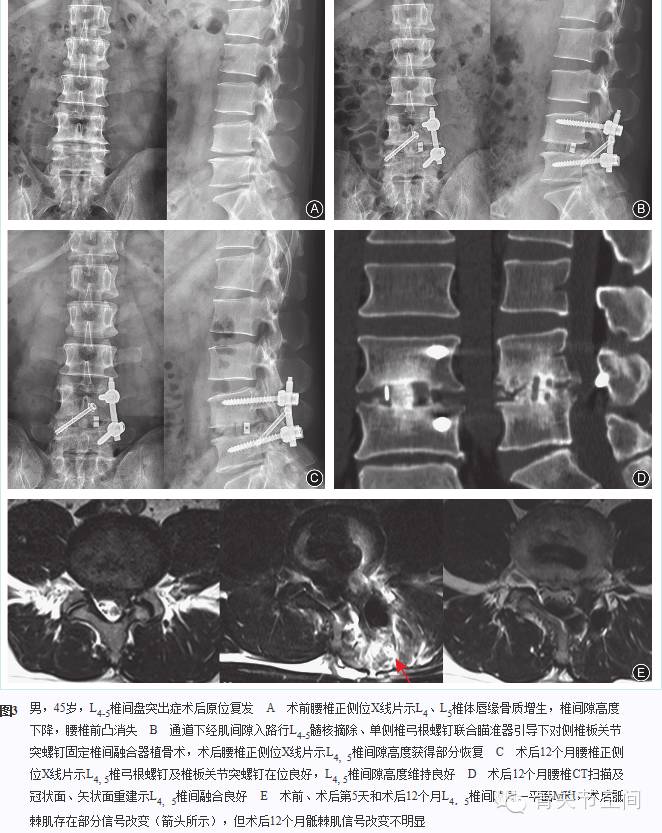

至随访期末,4例不能明确椎间融合,表现为椎间融合器内骨质稀疏,并可见透光线。其余72例均获得骨性融合(图3, 图4),融合率为94.7%(72/76)。未观察到固定部位邻近节段明显的退变征象。椎板关节突螺钉固定侧关节突出现不同程度的骨融合。随访期间出现终板切割、融合器部分陷入椎体内6例,未影响植骨融合,此6例融合时间为(14.5±3.51)个月。未发现椎弓根螺钉与椎板关节突螺钉松动、移位、断裂或椎间融合器前后向移位。

五、影像学评价

常规于术后第3~5天、3个月、6个月、12个月及以后每年一次行腰椎正侧位X线检查,术后12个月行腰椎过屈过伸位X线检查;术后第3~5天行腰椎CT扫描,术后12个月行腰椎CT扫描及矢状面、冠状面重建;36例于术后12个月行腰椎MR检查。测量术前和术后病变节段椎间隙高度、腰椎冠状面和矢状面Cobb角、多裂肌损伤面积与程度,评估椎弓根螺钉和椎板关节突螺钉位置、椎间融合情况,观察椎弓根螺钉和椎板关节突螺钉有无松动、断裂及椎间融合器前后向移位征象。